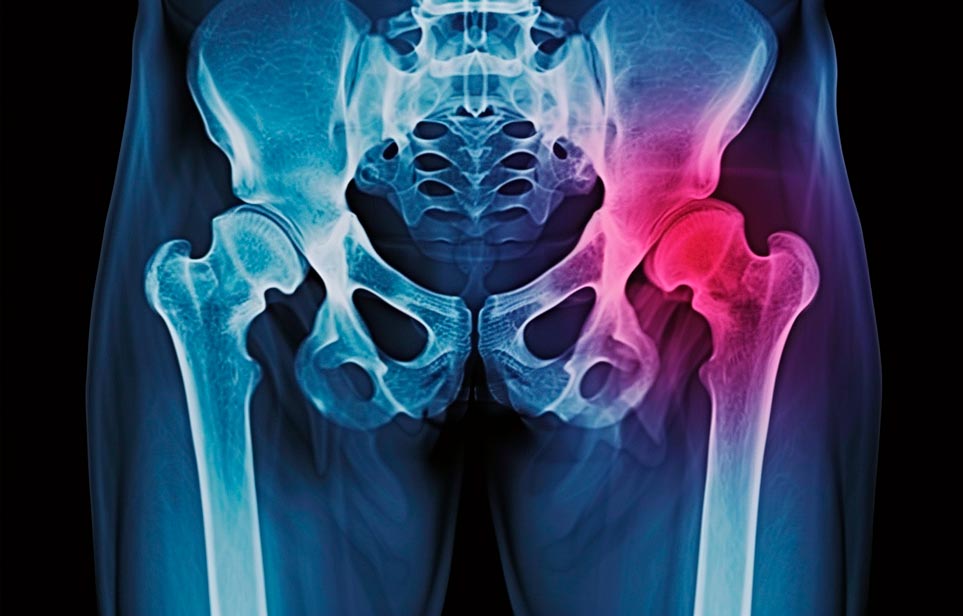

Реабилитация пожилых после перелома шейки бедра в Севастополе

Эффективная и профессиональная реабилитация после перелома шейки бедра в Севастополе осуществляется по демократичным ценам лучшими специалистами современной медицинской клиники «Заботливые люди» с применением персонального подхода к каждому пожилому человеку с такой тяжёлой травмой бедренной кости ноги. В процессе осуществления такой специализированной услуги все наши пациенты имеют возможность получения качественного и достойного обслуживания, эффективного восстановления. Лучший дом престарелых позаботиться о Вашем близком человеке.

Такая травма в большей части случаев возникает у граждан преклонного возраста. При её появлении на протяжении длительного времени сохраняются болевые и неприятные ощущения в области паха, при которых серьёзно ухудшается качество жизни, возникает множество последствий для его жизни и здоровья.

По какой симптоматике можно определить перелом шейки бедра?

Выявить его можно по возникновению следующей тревожной симптоматики:

- Визуально повреждённая нога сокращается на несколько сантиметром из-за сокращения мышц.

- Стопа выворачивается наружу.

- В лежачем положении человек не может поднять ногу.

При такой симптоматике важно незамедлительно обращаться к специалистам для получения всей необходимой помощи, терапии и восстановления после перелома шейки бедра. Если не оказать помощи старику, то это приведёт к гноению, инвалидности, иным видам осложнений.